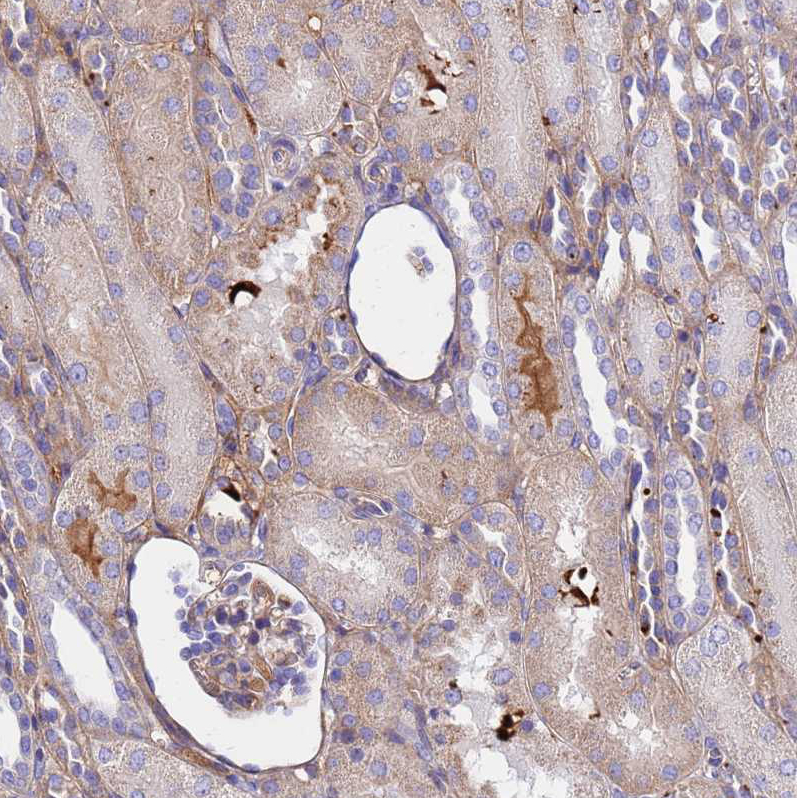

Immunohistochemical staining of human testis shows strong positivity in secretion.